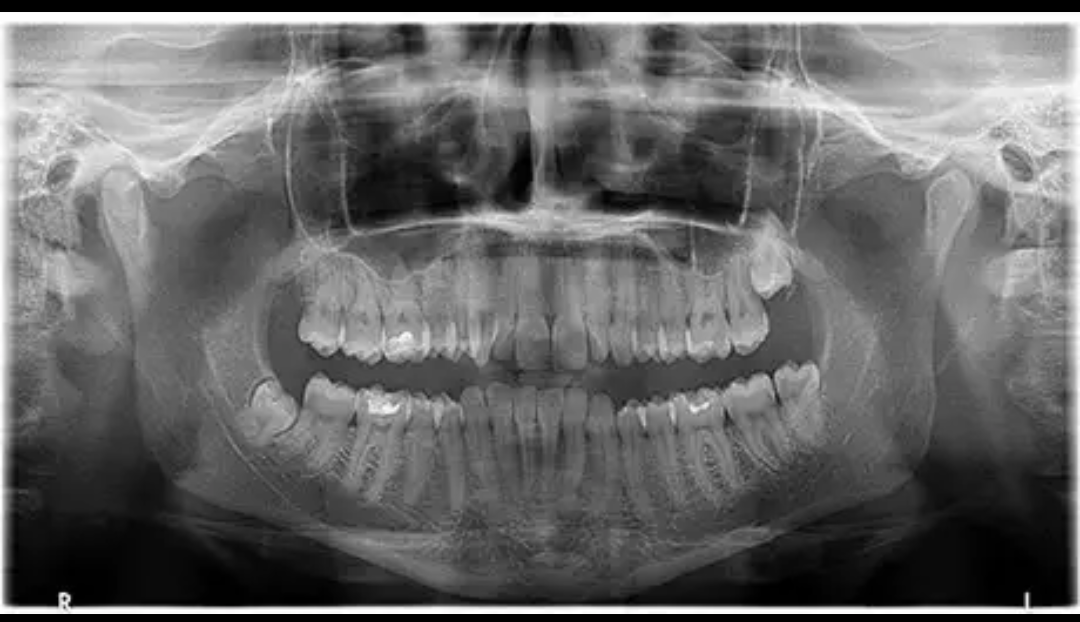

това за секторна рентгенова снимка ли се счита (не е моя)?  в какви случаи се препоръчват 3D и панорамните?

Не. това е панорамна

Здравейте, има ли нещо притеснително в горния десен мъдрец?